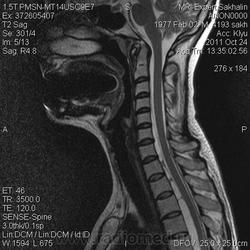

МРТ ШОП

Женщина с жалобами на боли в пояснице, но решила обследовать весь позвоночник.Травм, операций не было.Такие же изменения в грудном отделе.

1. Субархноидальная киста

2. Лизированная субдуральная гематома.

3. Менее вероятнее эпиема (но это только при условии соотвествующей клиники...)

Думаю все же №1... № 2 - это запасной вариант. Послушаем, что скажет общественность

Мультилокулярная экстрадуральная менингеальная киста